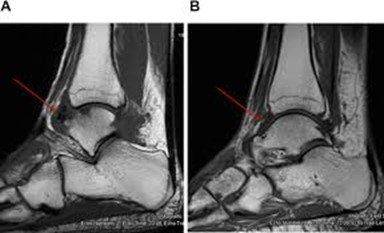

Mri showing arthrofibrosis of ankle

- Fibrosis refers to thickened, stiff scar tissue that develops after trauma or surgery. It limits flexibility and causes discomfort, especially during movement.

- Common in people who have sustained significant injuries like ligament tears, fractures, or surgeries that left scarring.

- Symptoms include restricted movement, a tight sensation, and pain during activity. Fibrosis can also contribute to instability.